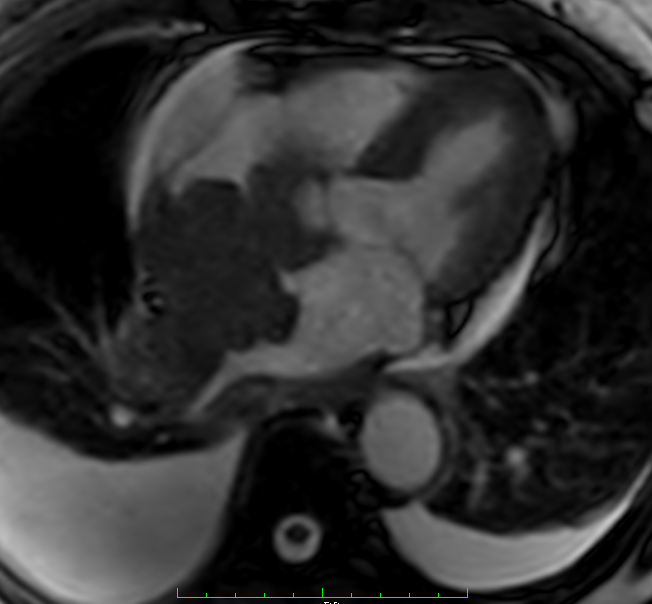

Short axis evidencing the mass invasion.